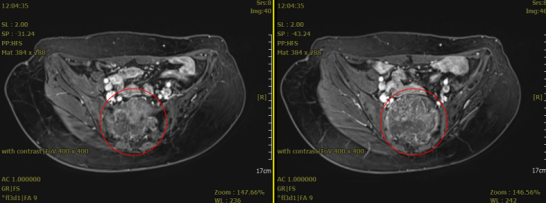

患者王**,女性,52岁,黎族,诊断:骶尾部脊索瘤。治疗前评估:MR-骶2-4椎体部分骨质破坏,相应平面见大小约8.8x7.1cm(S6,I57)混杂T1、混杂长T2肿块影,向盆腔内生长,局部侵及骶管,边界尚清;病灶约270度的范围内紧临结直肠。

2023年3月(碳)离子治疗前核磁检查,红圈内为肿瘤

2023年3月(碳)离子治疗前核磁检查,红圈内为肿瘤